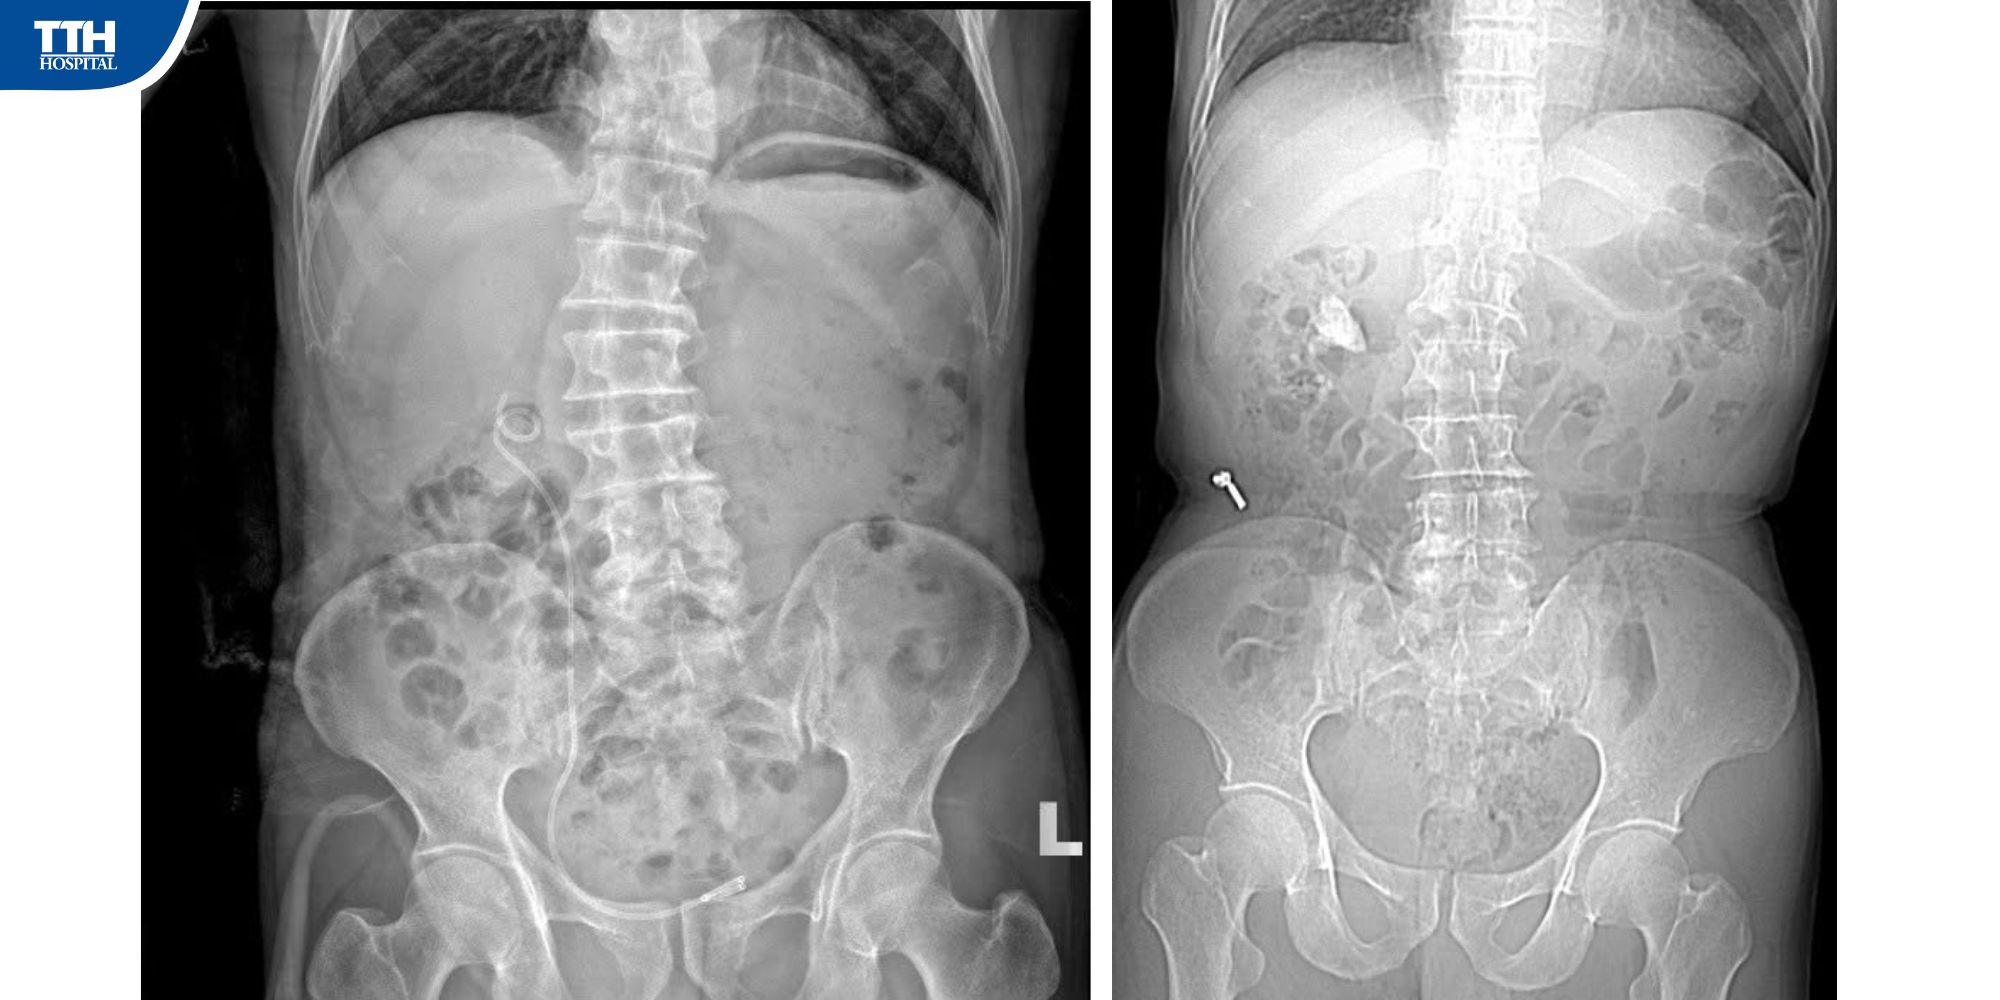

⭐ Ông N.T.N (72 tuổi) nhập viện trong tình trạng đau hông lưng phải, tiểu buốt. Sau thăm khám, các bác sĩ nhận định đây là tình trạng nguy hiểm và có thể dẫn đến suy thận nếu không được can thiệp kịp thời.

Nhờ ứng dụng kỹ thuật hiện đại, tán sỏi thận qua da trở thành giải pháp phù hợp: ít đau, ít xâm lấn, hiệu quả cao và phục hồi nhanh.

🔹 Vết mổ nhỏ - xử lý gọn sỏi lớn 3cm

Bác sĩ chỉ cần tạo một lỗ nhỏ khoảng 1cm ở vùng hông lưng để đưa ống nội soi vào tán vụn sỏi bằng laser. Các mảnh sỏi nhỏ được hút ra qua cùng đường hầm này, giúp người bệnh gần như không đau, ít chảy máu và có thể xuất viện sau 3-5 ngày.